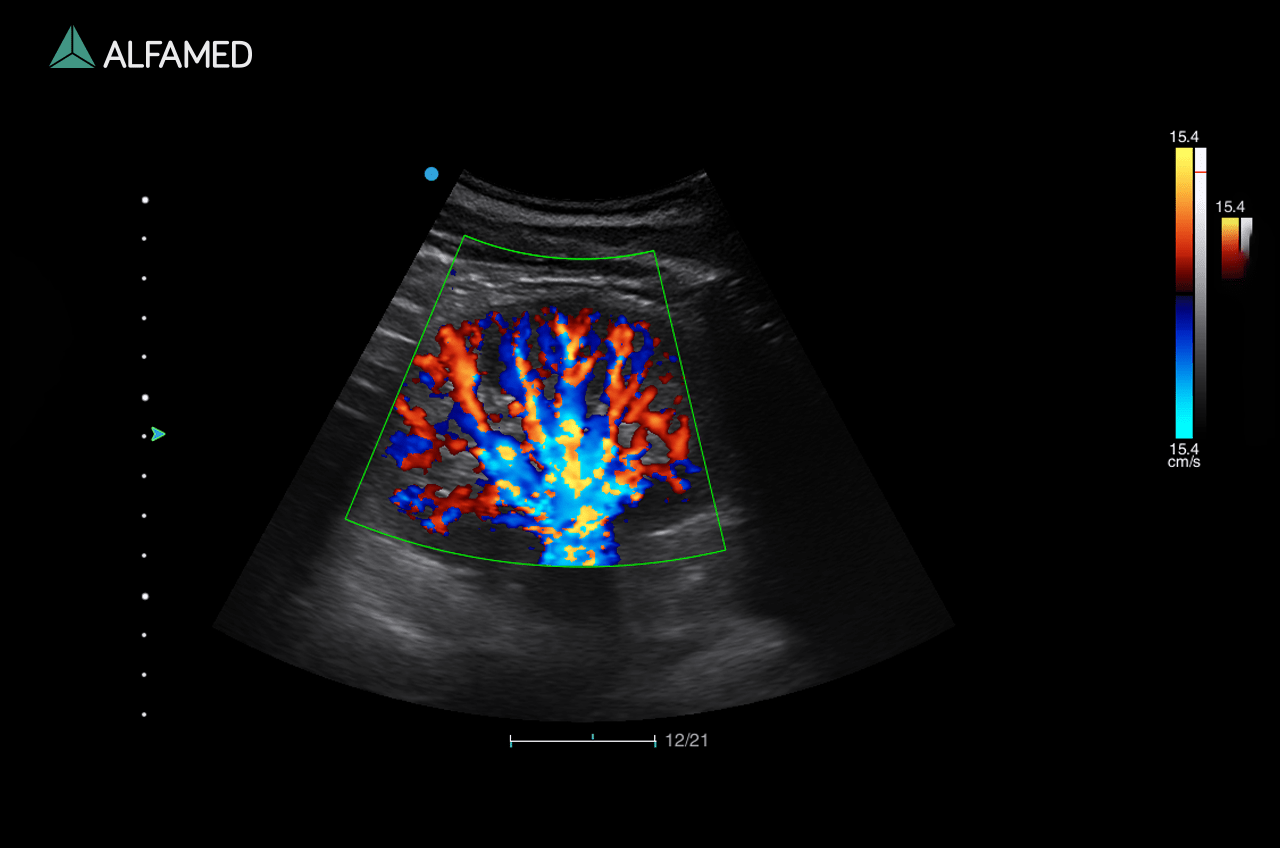

Dotado de softwares avançados e transdutores específicos, o Magnus X5 apresenta alta versatilidade para imagem geral e excelente performance, principalmente, nos exames de cardiologia avançada e obstetrícia.

- Panoscope com Color

- VS Flow